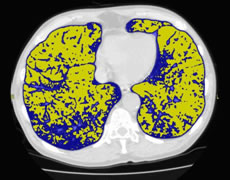

胸部CT検査:9,900円(税込)

胸部レントゲンではわかりづらい小さな病変を映し出すことが可能で、肺がんを発見するのに役立つ検査です。

肺気腫検査(ラングビジョン)

肺気腫はおもにたばこが原因で、正常な肺胞が破壊される恐ろしい病気です。

肺全体のCT画像を解析し、肺気腫の部分を抽出してその状態や程度をより高い精度で評価する検査です。

胸部CT検査 + 肺気腫検査 12,100円